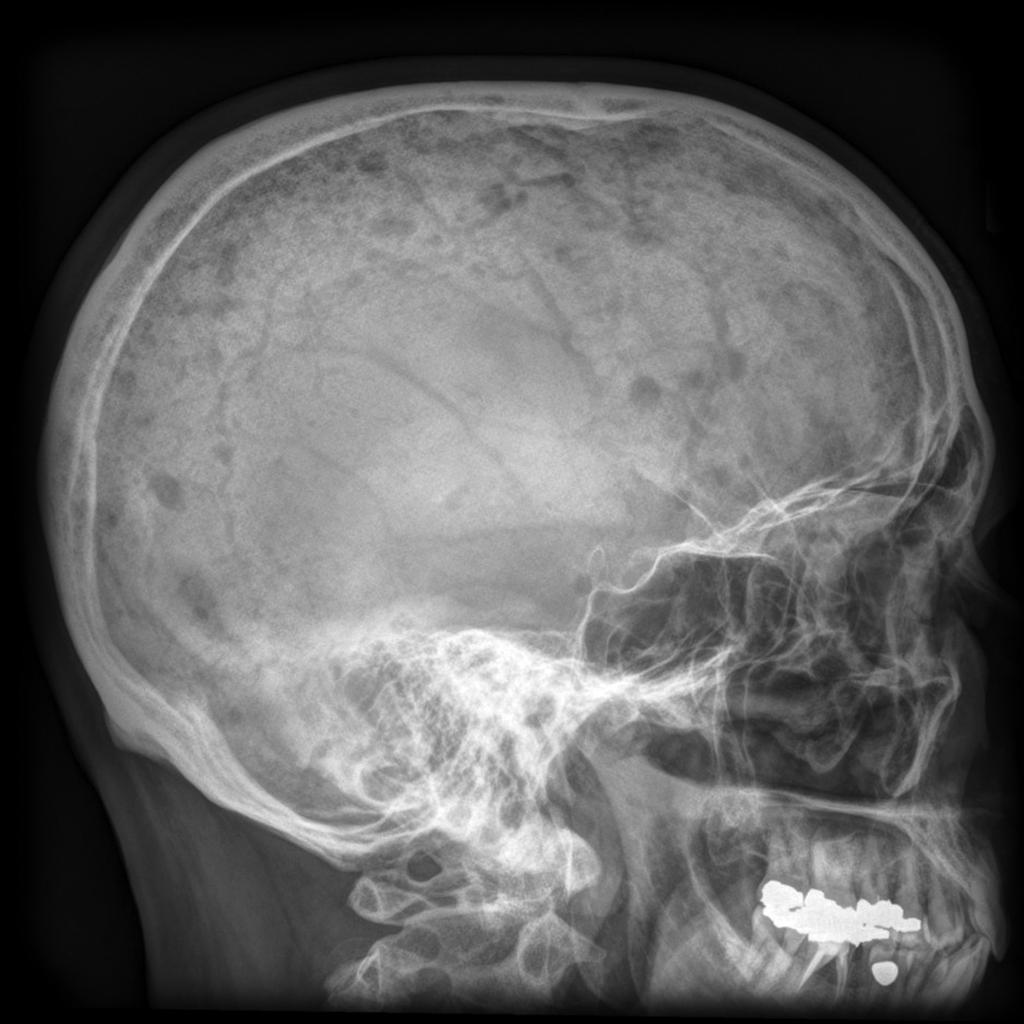

Myeloma causes bone destruction (osteolytic lesions, painful ‘holes’ in the bone). The growth of myeloma cells hinders the normal function of bone-building cells (osteoblasts). In addition, the activity of cells that normally remove worn bone tissue (osteoclasts) is increased. This imbalance of making new and removing old bone tissue caused by myeloma leads to bone destruction. There may be a single lesion or, more commonly, multiple locations (multiple myeloma). In the maxillofacial region the bone lesions predominantly affect the skull and less often the jaws (see Figure 1).

Figure 1: Multiple bone lesions of the skull caused by multiple myeloma; this appearance is sometimes referred to as ‘pepper pot’ skull. Case courtesy of Prof Frank Gaillard, Radiopaedia.org. From the case rID: 7682.